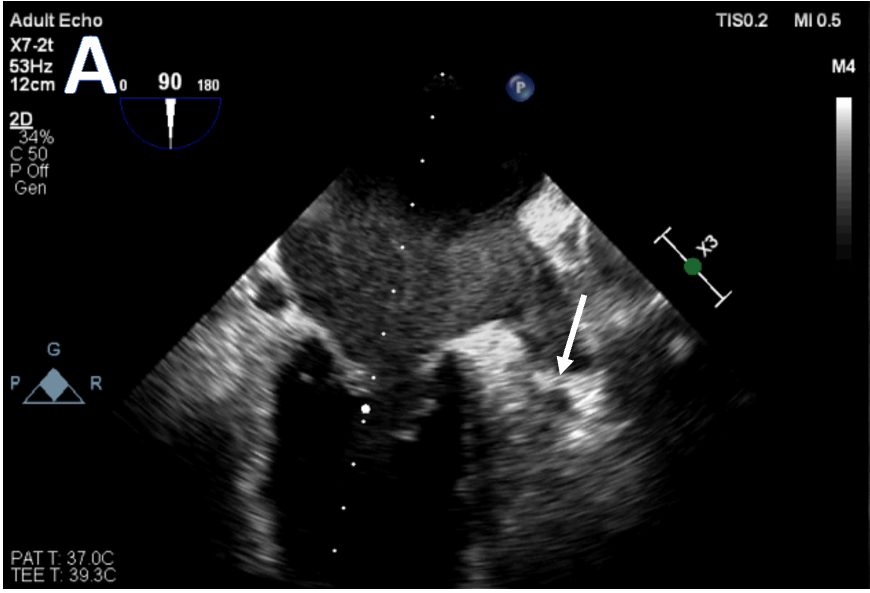

✨ Video of the Week: Transcatheter Treatment of a Large Saphenous Vein Graft Aneurysm ▶️hubs.ly/Q04f3G2f0